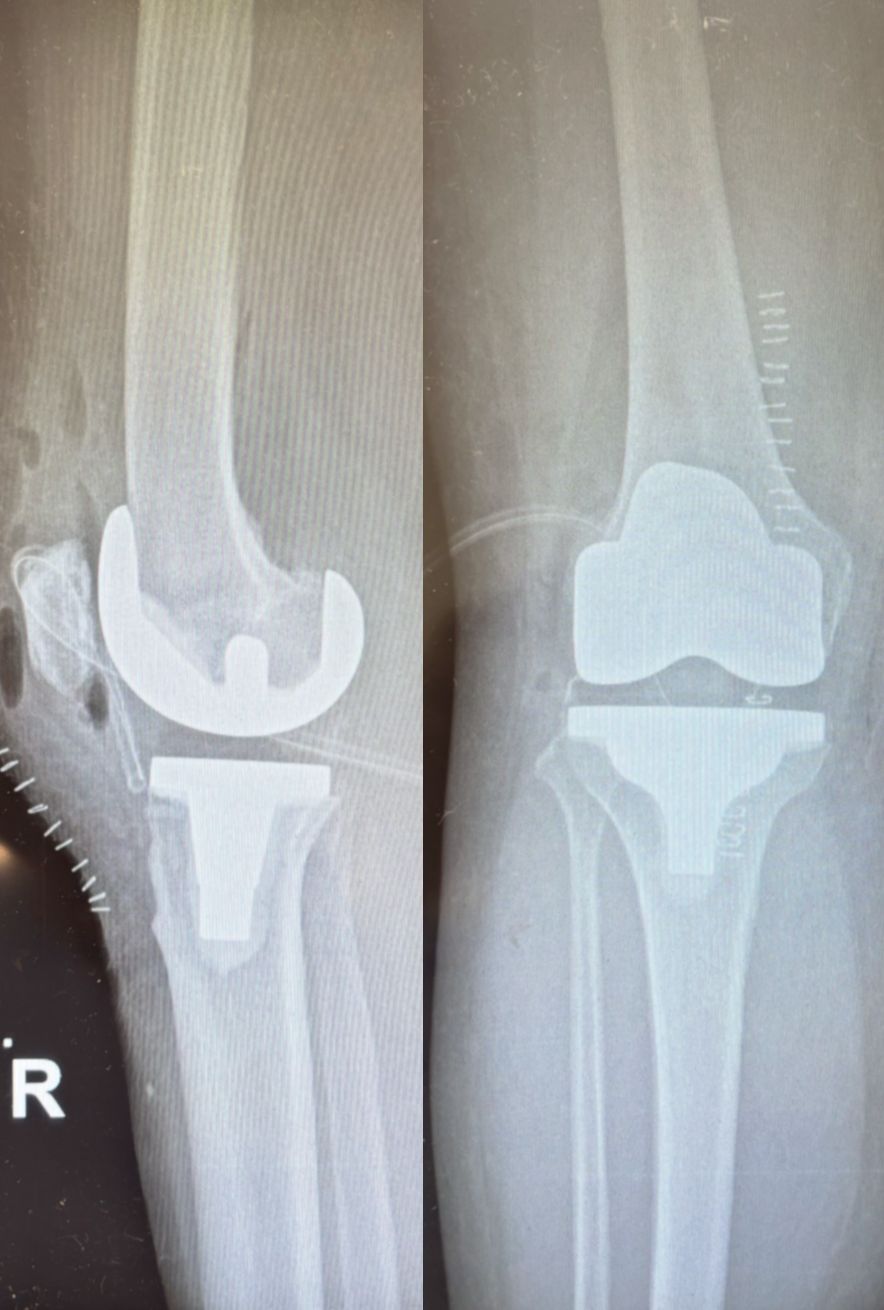

Ho maturato una solida esperienza nella chirurgia protesica mini-invasiva di anca e ginocchio. Eseguo interventi di protesi di anca mediante accesso anteriore “bikini” e accesso posterolaterale, interventi di protesi di ginocchio sia monocompartimentale che totale. Tratto la traumatologia sportiva di ginocchio e spalla mediante l’utilizzo di tecniche artroscopiche mini-invasive.